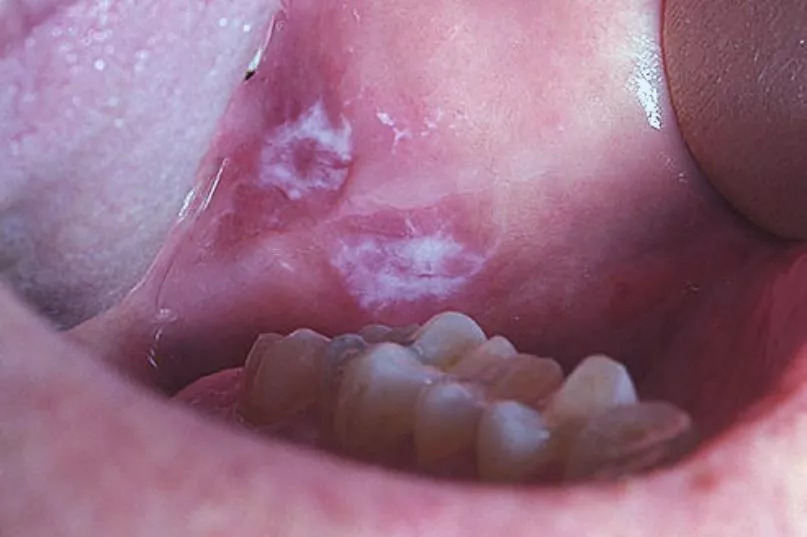

3. Xuất hiện các mảng trắng hoặc đỏ không biến mất

Trước khi phát triển thành vết nhiệt miệng rõ ràng, ung thư khoang miệng có thể bắt đầu bằng các tổn thương tiền ung thư (tiền ác tính) dưới dạng mảng màu bất thường, thường bị nhầm lẫn với nấm hoặc đổi màu niêm mạc.

Nhiệt miệng mà có 3 đặc điểm này e rằng "che giấu" tế bào ung thư, khám ngay còn kịp!- Ảnh 2.

Ảnh minh họa

Cụ thể là các mảng trắng (Leukoplakia) có màu trắng xám, dày, thường không gây đau, hoặc các mảng đỏ (Erythroplakia) có màu đỏ tươi, nhung. Nếu bạn nhận thấy bất kỳ mảng trắng hoặc mảng đỏ nào không thể cạo đi được và không biến mất trong vòng 2 tuần, cần phải đi kiểm tra ngay lập tức. Đây là dấu hiệu cảnh báo sớm nhất của sự phát triển tế bào ác tính.